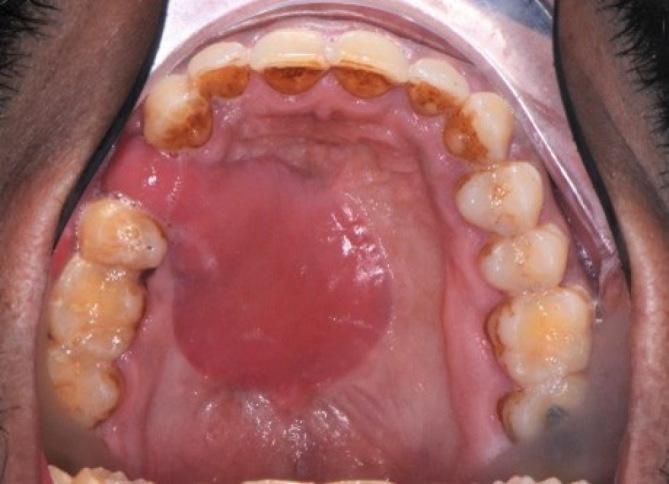

To present a new protocol for closure of cocaine fistulae using a combination of palatal flap delay and facial artery musculomucosal flap demonstrating its reliability for closing these challenging defects and its advantages compared to the other used techniques such as turned over palatal, tongue, temporalis muscle, and radial forearm free flaps.

METHODS

Eight patients presenting with oronasal communication who admitted sniffing cocaine were treated using palatal flap delay in combination with facial artery musculomucosal flap after quitting cocaine abuse. All cases were followed up for a period of 12-18 months where healing pattern, signs and symptoms of breakdown, recurrence, or residual fistulae in addition to patient satisfaction using a visual analog scale were evaluated.

RESULTS

All eight patients showed a very good healing pattern without any signs and symptoms of breakdown, recurrence, or residual fistulae. VAS assessment for patient satisfaction where 10 being the most satisfied showed that four patients reported score 10, three reported score 9, and one reported score 8.

CONCLUSIONS

The combination of palatal flap delay and FAMM flap is very reliable for cocaine fistulae closure.